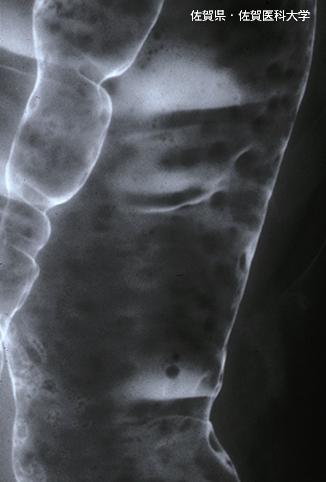

Posted by: Saga Pref., 佐贺医科大学 (Dr. 水口)

疾病(病理主体)的分类恶性淋巴系肿瘤/恶性淋巴瘤

部位(按器官分)大肠/降结肠

检查方法X线

肿瘤最大直径1~9

多发性肿瘤(同一器官)有(同时性)